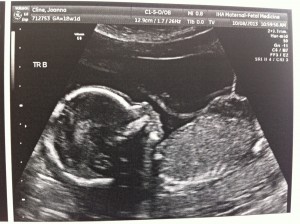

Hello! I had my bi-weekly ultrasound today and, if a triplet pregnancy appointment could be uneventful, this one was it!

Everything still looks great. The triplets are growing but we won’t have another growth scan until my 22wk appointment. Heart beats look good and it’s clear they’re getting bigger (Today’s pictures attached.)